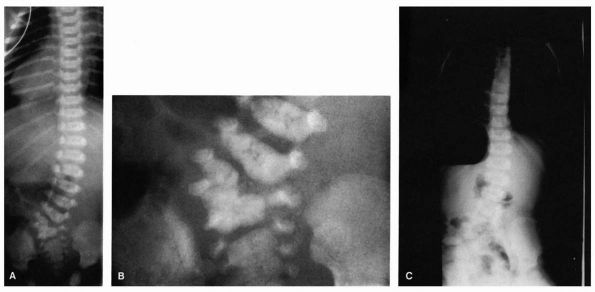

FIGURE 16-9. (A) Juvenile idiopathic scoliosis in a 7½-year-old boy with an 80° thoracic curve that progressed despite bracing. (B)

Same patient at age 8 years and 11 months. Curve is maintained at 41° with distraction instrumentation and fusion at hook sites. Patient is wearing TLSO external support. Definite surgery is planned at puberty. (C) A 7½-year-old girl with juvenile onset scoliosis; she was initially treated in a brace but her curve progressed (D), necessitating anterior and posterior fusion (E). |

in this group if progression occurs despite bracing (Figure 16-9).